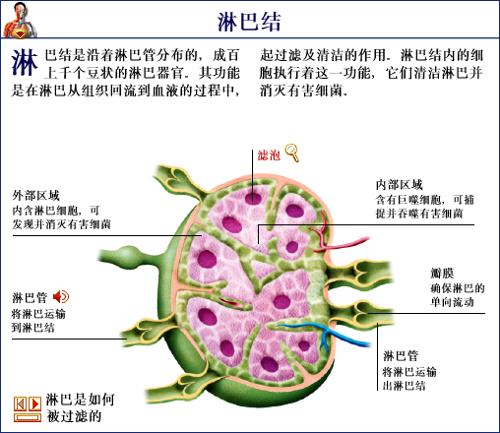

淋巴结干酪样坏死 – 人体病理-其他产品-产品中心 – 生物科普标本_中草药标本_生物显微玻片标本_新乡市求精教学仪器有限公司